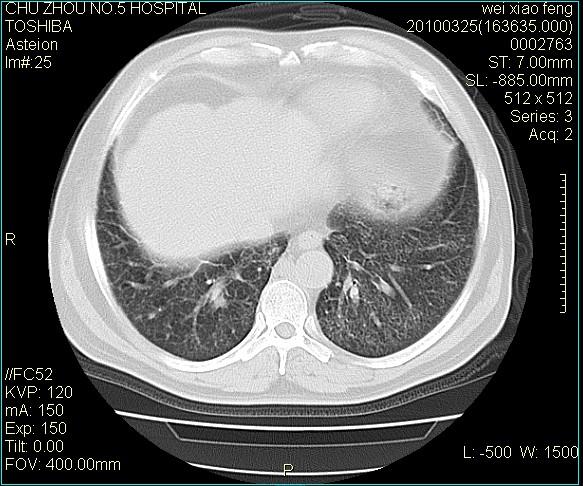

男,60岁,反复咳、痰、喘3月,加重3天。

双肺间质性改变。

考虑双肺血型潘散肺结核/

间质性肺炎伴间质纤维化!不排除伴有职业病!

急性血型潘散肺结核。

双肺间质纤维化,双肺血型潘散肺结核。

考虑间质性肺炎伴间质纤维化。

右肺中叶结节影为原发灶,考虑右肺中叶周围型肺癌并淋巴道转移